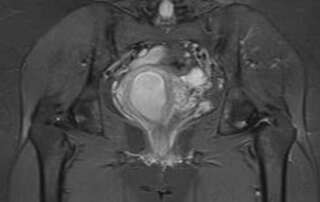

Haematometra following a caesarean section: a rare and avoidable complication